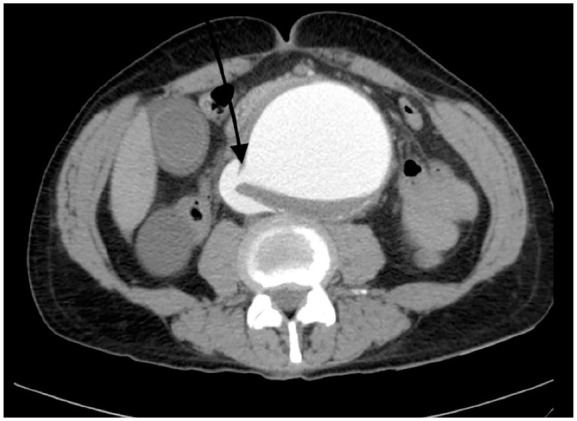

Abdominal aortic aneurysm (AAA) is a potentially life-threatening condition characterized by abnormal dilation of the abdominal aorta, typically due to chronic arterial wall degeneration. Aorto-caval fistula (ACF) is a rare but serious complication of AAA, occurring in less than 1% of cases overall, with incidence increasing in the setting of rupture. ACF involves the formation of an abnormal communication between the abdominal aorta and the inferior vena cava (IVC), resulting in blood shunting from the arterial to the venous system. This can cause reduced organ perfusion, high-output cardiac failure, and multiorgan dysfunction. We present the case of a 65-year-old hypertensive male with a known AAA who presented with 2 days of abdominal pain but no systemic or gastrointestinal symptoms. Physical examination revealed periumbilical tenderness, while laboratory results were normal. Contrast-enhanced computed tomography of the abdomen revealed a large (10 cm) infrarenal AAA with evidence of rupture, mural thrombus, and a fistulous connection to the IVC. The patient underwent successful endovascular repair with complete resolution of the aneurysm and fistula, as shown in follow-up imaging. This case highlights the importance of high clinical suspicion and the role of early imaging in diagnosing ACFs, even in the absence of classical signs or lab abnormalities. The aim is to raise awareness of such atypical presentations and emphasize our case's uniqueness in its silent, stable, yet severe presentation.

Abstract Image